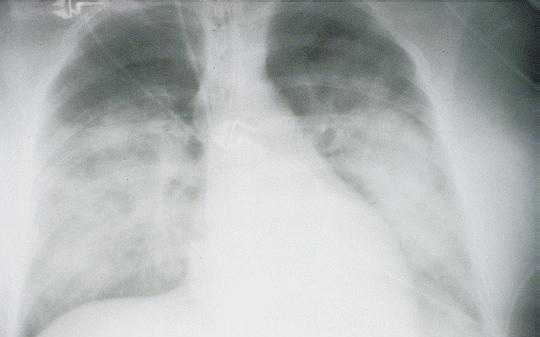

Radiologic Findings

HPS has a characteristic radiological evolution, beginning with minimal changes of interstitial pulmonary edema, progressing to alveolar edema with severe bilateral involvement. Pleural effusions are common and are often large enough to be evident radiographically. Heart size is usually normal. Cardiac silhouette size on chest radiographs is usually normal.

Approximately one-third of patients show evidence of pulmonary edema in the initial radiograph. Forty-eight hours after the initial radiograph, virtually all patients demonstrate interstitial edema and two-thirds have developed extensive bibasilar or perihilar airspace disease.

The lack of peripheral distribution of the initial airspace disease, the prominence of interstitial edema and the presence of pleural effusions early in the disease process help distinguish HPS from ARDS. There is, however, overlap in the radiographic appearance of the two diseases. Atypical pneumonias such as that caused by mycoplasm pneumonia can produce radiographic findings similar to early HPS, although the clinical illness tends to be much less severe.